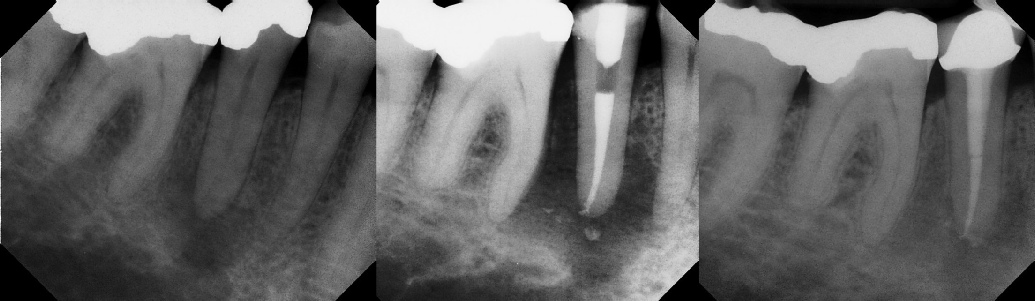

COMPLICATED ANATOMY LARGE LESIONS CALCIFIED CANALS PERFORATION / RESORPTION SEPARATED INSTRUMENTS SURGICAL CASES RETREATMENT / pOST REMOVAL OPEN APICES ACCESS THRU CROWNS Root Canal Case Portfolio

Pre-op Post-op 6 mos.